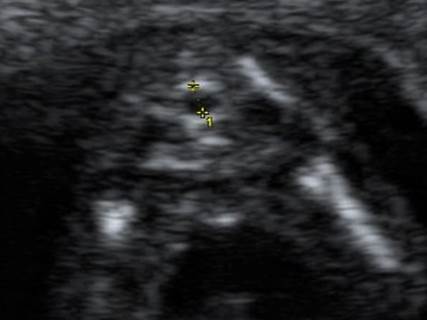

Вопрос 1

Это один случай в разные сроки в 12 и 21 неделю. Какой диагноз?

Ответ на вопрос 1

• Случай двойной атрезии — пищевода и 12-перстной кишки

• Признак «замкнутого» желудка, он смещен, перерастянут, симметричен (Travel подушка)